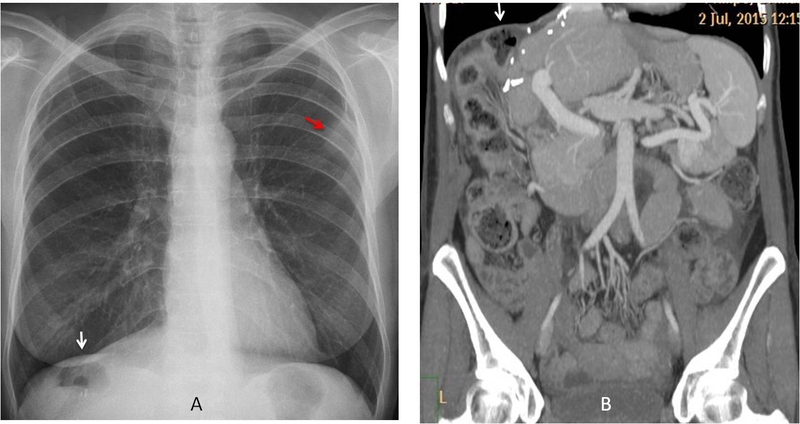

Phương pháp này rất phổ biến để xác định thủng tạng rỗng, thường được sử dụng trong các trường hợp cấp cứu. Người bệnh sẽ được hướng dẫn chụp X-quang bụng ở tư thế đứng hoặc nửa nằm nửa ngồi để phát hiện hơi bên dưới cơ hoành.

Dùng cho những bệnh nhân khó xác định thủng tạng rỗng qua siêu âm hoặc X-quang.

Hình ảnh từ phim chụp CT có thể xác định thủng tạng rỗng dựa vào các dấu hiệu như: